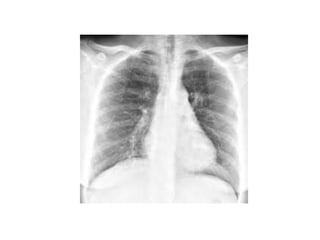

• If pneumonia is suspected, a chest X-ray may be

ordered.